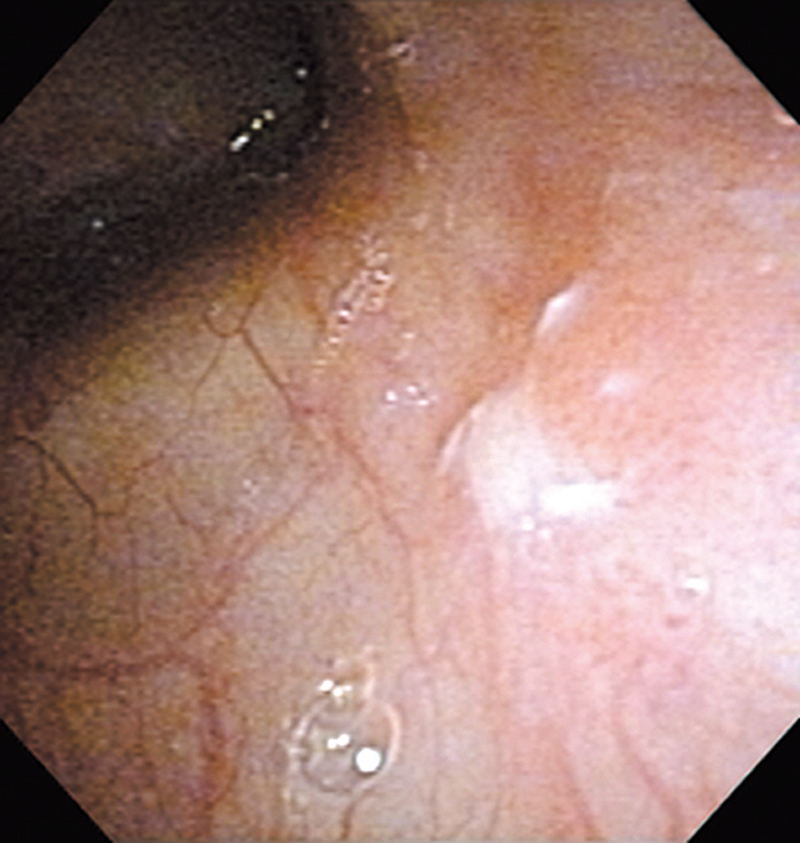

Hypopharynx Cancer (Right Pyriform Sinus) Aged 57, male

white light

The lesion was detected on the right pyriform sinus in a head/neck cancer screening with NBI laryngopharyngoscopy before an esophageal carcinoma surgery.

The NBI image showed an irregular shaped brownish lesion. In the conventional white light image, a slight reddening was observed but the boundary was hard to identify.

The lesion was 9 x 6 mm, treated with endoscopic mucosal resection and diagnosed as a carcinoma in situ.